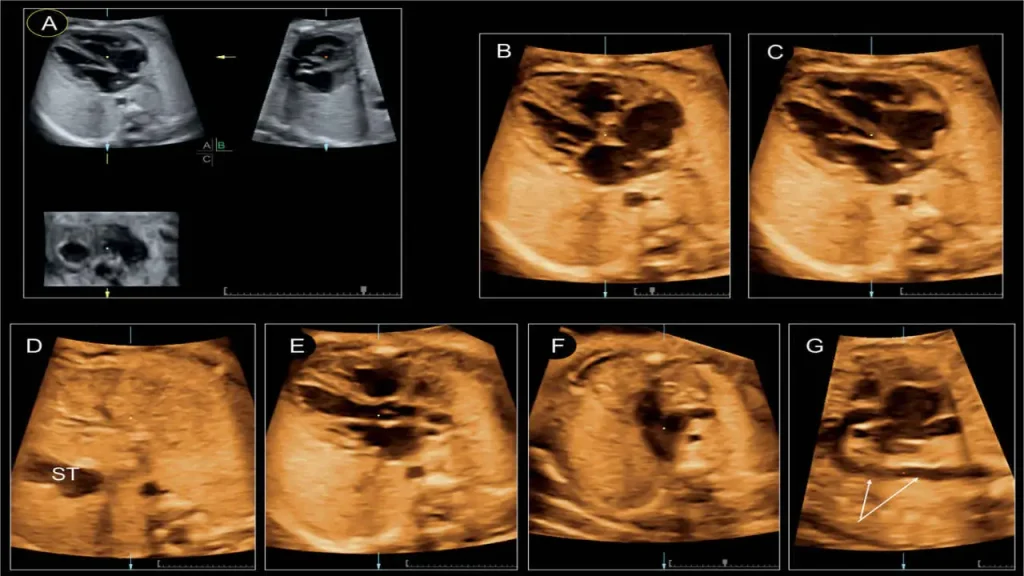

- اکوی جنینی: برای بررسی قلب جنین در دوران بارداری و تشخیص زودهنگام مشکلات احتمالی.

کلینیک ویستان از دستگاههای اکوکاردیوگرافی پیشرفته سهبعدی بهره میبرد که تصاویر واضح و دقیقی از ساختار و عملکرد قلب ارائه میدهند. این تجهیزات به پزشکان امکان میدهند حتی جزئیترین ناهنجاریها را تشخیص دهند و برنامه درمانی مناسبی تدوین کنند.

- تصویربرداری دقیق و سهبعدی قلب کودک

- اندازهگیری دقیق جریان خون و عملکرد دریچهها

- امکان انجام اکو جنینی برای تشخیص مشکلات قلبی در دوران بارداری ( بهترین مراکز اکو قلب جنین را بشناسید)